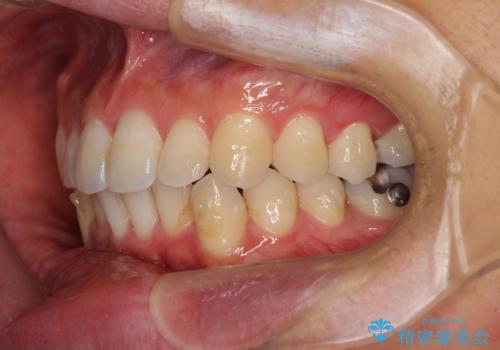

口が少し閉じにくい インビザラインによる非抜歯矯正

- 口元の突出感を治したいとのことで来院された患者様です。

上下顎ともにIPR(歯と歯の間を削る)と歯列全体の拡大によって口元が引っ込むように設計し、インビザラインにより治療を行うこととしました。

抜歯をして口元を下げなければならないほど出っ歯ではなかったため、少しずつ治療ゴールを変更しながら仕上げていきました。

気になっていた前歯の飛び出した印象は、最終的にはスッキリと引っ込み、大変満足していただきました。